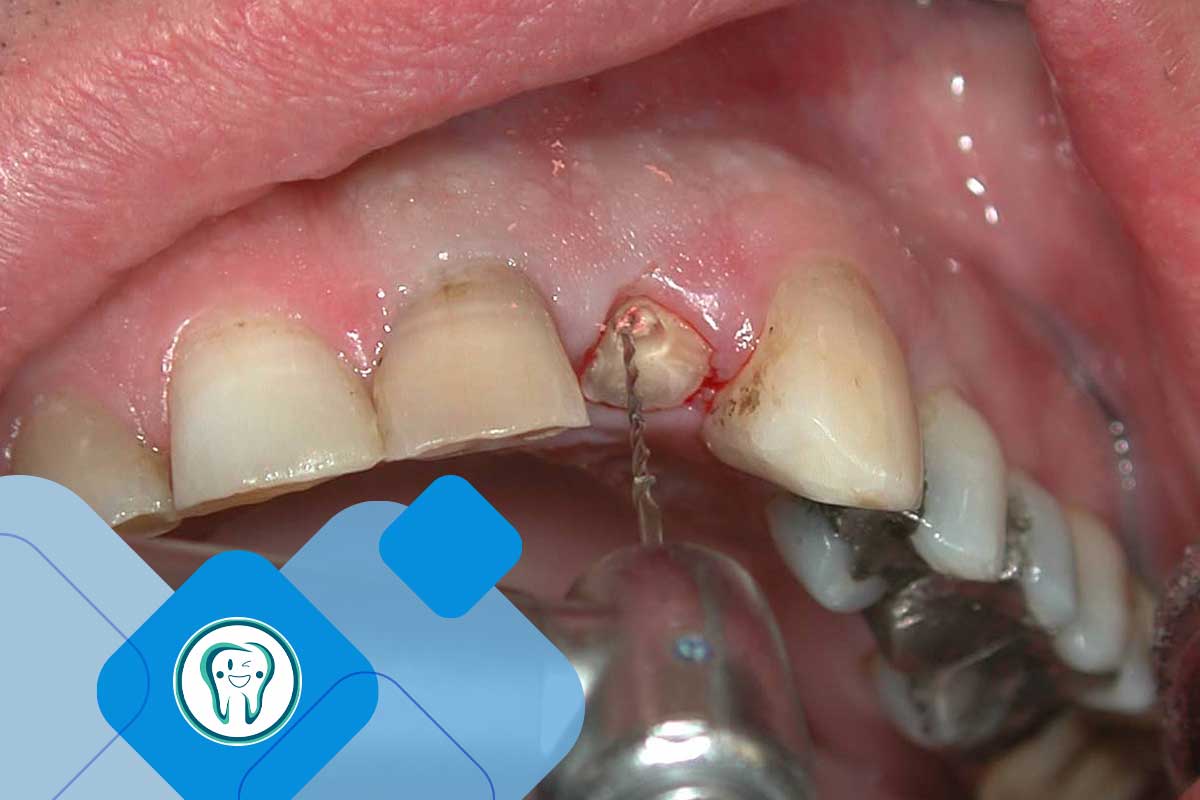

1. ایمپلنت فوری (همزمان با کشیدن دندان): در این روش، در همان جلسه‌ای که دندان آسیب دیده به دقت خارج می‌شود، پایه ایمپلنت (فیکسچر) درون حفره قرار می‌گیرد. این روش برای دندان‌های جلویی که جنبه زیبایی دارند بسیار پرطرفدار است، اما نیازمند استخوان فک متراکم و عدم وجود عفونت است.

تجربه ایمپلنت آقای رضا برهانی در کرج

برای درک بهتر روند کار، اجازه دهید به یک پرونده واقعی از بیماران کلینیک دکتر بیاتی اشاره کنیم. آقای رضا برهانی، مردی ۴۵ ساله، به دلیل شکستگی عمودی دندان آسیاب اول (دندان شماره ۶) به کلینیک مراجعه کردند. شکستگی تا زیر لثه امتداد یافته بود و دندان قابل نگهداری نبود.

ایشان اصرار داشتند که همان روز دندان کشیده شده و ایمپلنت فوری انجام شود. اما در بررسی‌های رادیوگرافی (CBCT) مشخص شد که یک ضایعه عفونی کوچک در انتهای ریشه وجود دارد. همچنین دیواره خارجی استخوان فک ایشان بسیار نازک بود.

دکتر بیاتی با در نظر گرفتن ریسک بالای پس زدن ایمپلنت، به ایشان پیشنهاد ایمپلنت زودهنگام (Early) داد. دندان با کمترین آسیب کشیده شد، عفونت کاملاً تخلیه و پاکسازی گردید و داخل حفره مقداری مواد پیوند استخوان قرار گرفت. پس از گذشت ۶ هفته، لثه به طور کامل ترمیم شده بود و محیطی کاملا استریل و آماده فراهم بود. سپس پایه ایمپلنت در بهترین زاویه ممکن قرار داده شد و پس از ۳ ماه جوش خوردن کامل، روکش نهایی نصب گردید. امروز، پس از گذشت دو سال، آقا رضا بدون هیچ مشکلی با آن دندان غذا می‌خورد و از اینکه برای رسیدن به نتیجه قطعی و بدون ریسک کمی صبوری کرده، بسیار رضایت دارد.